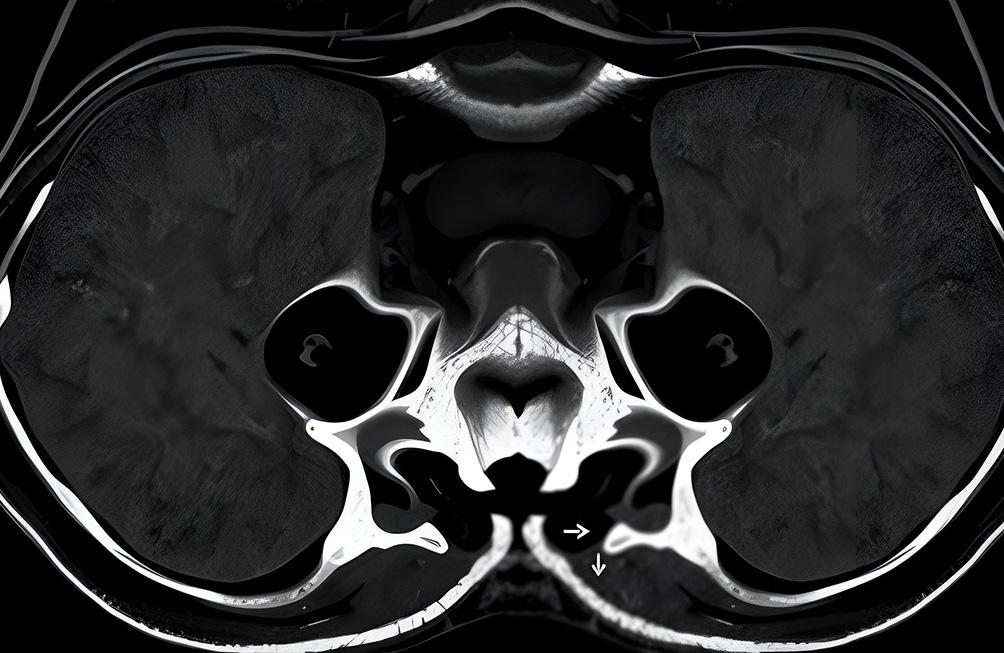

L'IRM pelvienne pour recherche d'endométriose est une méthode non invasive, qui facilite le diagnostic en fournissant des informations sur l'étendue de la maladie, sa localisation et ses éventuelles complications. L'IRM est souvent utilisée lorsque d'autres examens, comme l'échographie, ne permettent pas de confirmer le diagnostic ou de mieux visualiser certaines lésions.